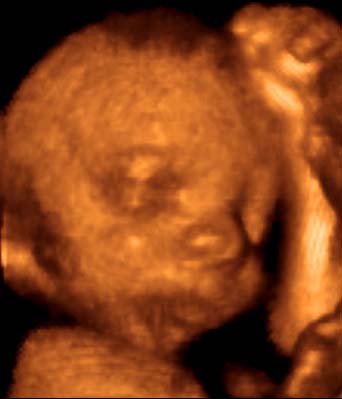

4D-ULTRAHANG

Fotógaléria / Arcok

A képeket Györfi Mátyás készítette.

26. hét

27. hét

29. hét

30. hét

31. hét